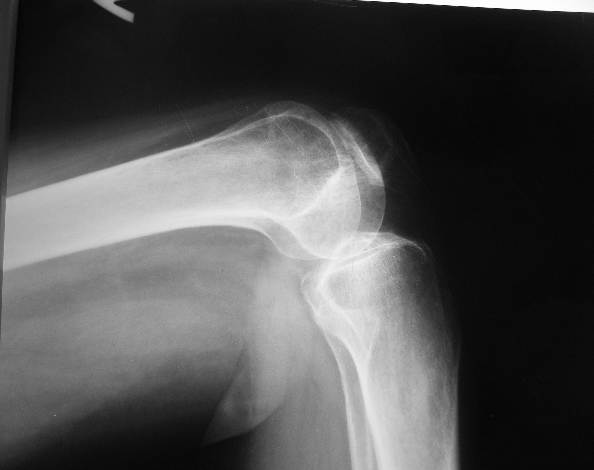

[Ortho] артроз коленного сустава

женщина 46 лет

май 2005 г заболел левый коленный сустав

Август 2005 артроскопия лечебно-диагностическая. Диагноз деформирующий

остеартроз хондромаляция1-2 степени

Февраль 2006 г артроскопическая резекция внутреннего мениска. Диагноз

застарелый разрыв внутреннего мениска на фоне гонартроза 2 степени.

Июнь 2007 артроскопия ревизия левого коленного сустава, резекция

поврежденной части внутреннего мениска, иссечение крыловидной  складки,

дебридмент коленного сустава. Диагноз застарелое повреждение

регенератавнутреннего мениска, патологическая инфрапателярная складка ,

комбинированная контрактура  левого коленного сустава, на фоне артроза 2

степени.

Октябрь 2007 МР графические признаки остеартроза коленного сустава и

бедренно-надколенного сочленения 2 степени, дистрофические изменения

сораненногозаднего рога медиального мениска и передней крестообразной

связки, кисты нижней трети диафиза бедренной кости, послеоперационных

изменений медиального  мениска.

Октябрь 2007 эндопротезирование предложили.

При осмотре  больная ходит хромая,  небольшой отек коленного сустава,

пассивные движеня в полном обьеме, активные разгибания до 160 градусов

безболезненны  далее разгибание резко болезненно . При пальпации

надколенника болезненность с внутреннего края при сдвигании его кнаружи.